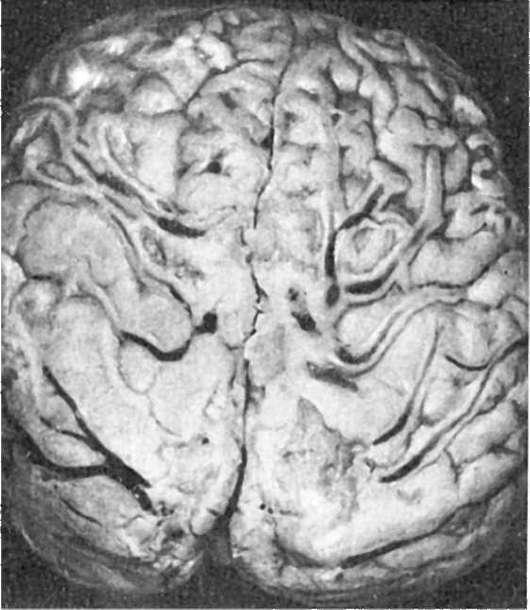

При менингококковом менингите мягкие мозговые оболочки в первые сутки от начала болезни становятся резко полнокровными, пропитаны слегка мутноватым серозным экссудатом. К концу 2-х-началу 3-х суток экссудат постепенно густеет, приобретает зеленовато-желтый цвет и гнойный характер. К 5-6-м суткам он еще более уплотняется от присоединения фибринозного выпота. Процесс начинается с базальной поверхности и переходит по перивенозным пространствам на выпуклую поверхность преимущественно

передних отделов полушарий большого мозга, располагаясь здесь в виде желтоватозеленоватого «чепчика» или «шапочки» (рис. 321). Гнойный процесс распространяется также на оболочки спинного мозга, где гной дольше остается жидким. Ткань мозга полнокровная, набухшая. Эпендима желудочков и сосудистые сплетения могут также вовлекаться в процесс с развитием гнойного эпендимита и пиоцефалии, которые чаще наблюдаются у детей первых 2-3 лет жизни.

Рис.

321. Менингококковый менингит. Гнойное воспаление локализуется преимущественно на поверхности полушарий большого мозга (по А.В. Цинзерлингу)